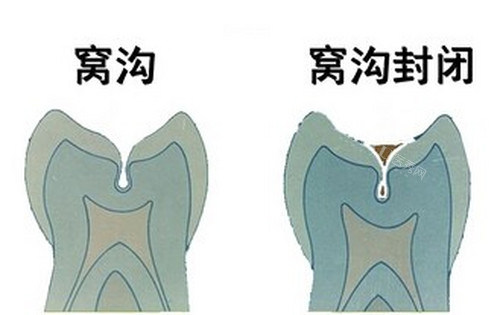

网友C:儿童窝沟封闭,守护孩子口腔健康

网友C的孩子正处于换牙期,她担心孩子会患龋齿,于是带着孩子来到了哈尔滨立远口腔做窝沟封闭。

“带孩子来看牙,我比较怕的就是孩子哭闹不配合,但立远口腔的医护人员真的太有耐心了。”网友C感慨地说,“他们用生动有趣的方式给孩子讲解口腔健康知识,还准备了小玩具和动画片,让孩子很快就放松了下来。整个窝沟封闭过程孩子都很配合,没有哭闹。医生操作很轻柔,孩子一点都没觉得疼。现在孩子的牙齿得到了非常好的保护,我也放心多了。立远口腔真的是一家很贴心的口腔诊所,以后孩子看牙我还选这里。”